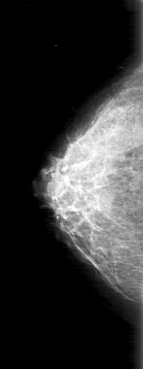

D_4025_1.LEFT_MLO

FILE: D_4025_1.LEFT_CC.OVERLAY

TOTAL_ABNORMALITIES 1

ABNORMALITY 1

LESION_TYPE MASS SHAPE LOBULATED MARGINS OBSCURED

ASSESSMENT 0

SUBTLETY 5

PATHOLOGY BENIGN

TOTAL_OUTLINES 1

BOUNDARY